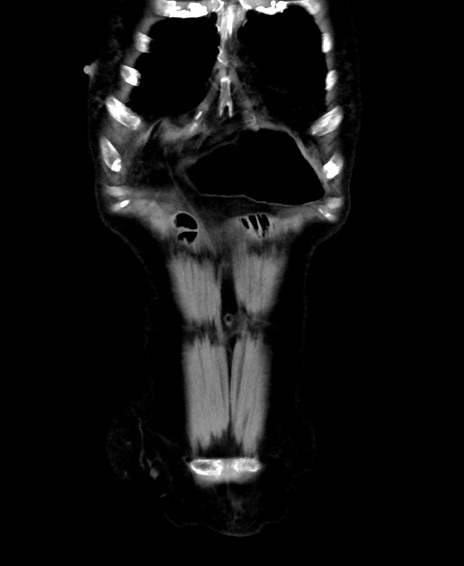

矢状断像